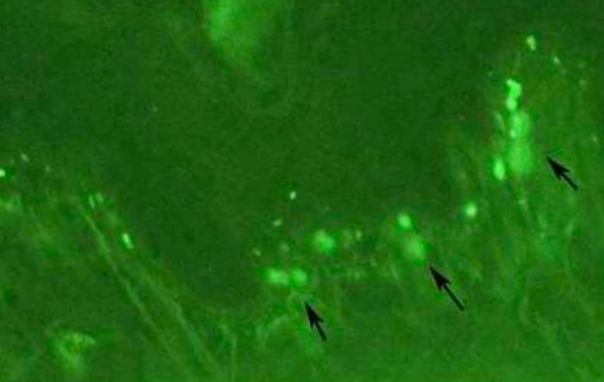

Lichenoid Contact Reaction amalgam (半抗原) LP,但只出現在有 amalgam 的位置、移除 amalgam 即消失。

Lichenoid Drug Reaction 藥物 非直接性 IgG 螢光染色 → string of pearls (沿著複層鱗狀上皮的 basal cell layer 細胞膜) alt text